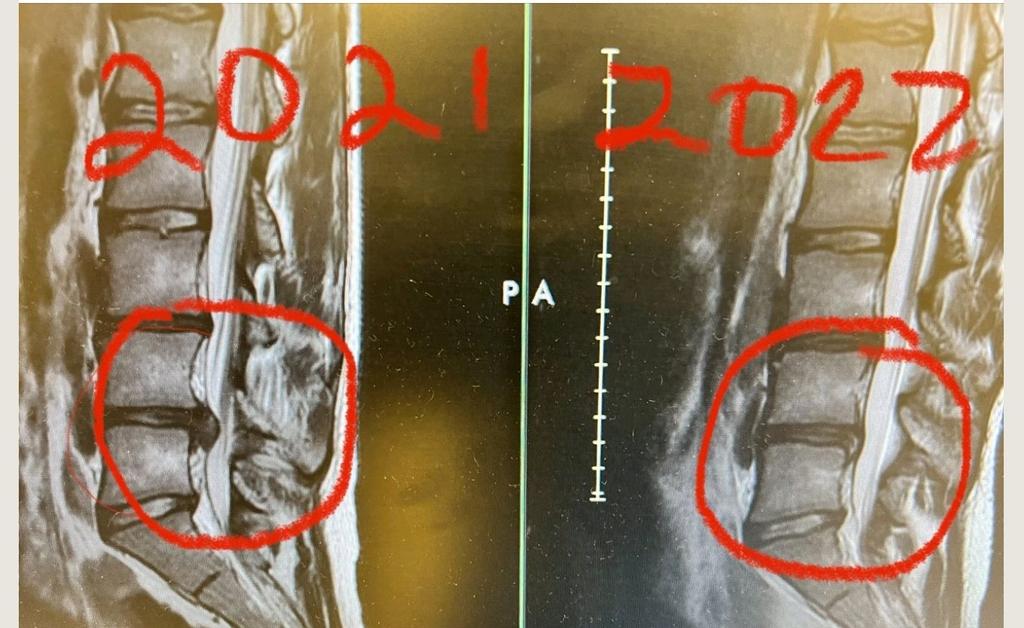

السؤال الان هل الغضروف المنزلق هو سبب الالم؟

قولا واحدا الجواب لا